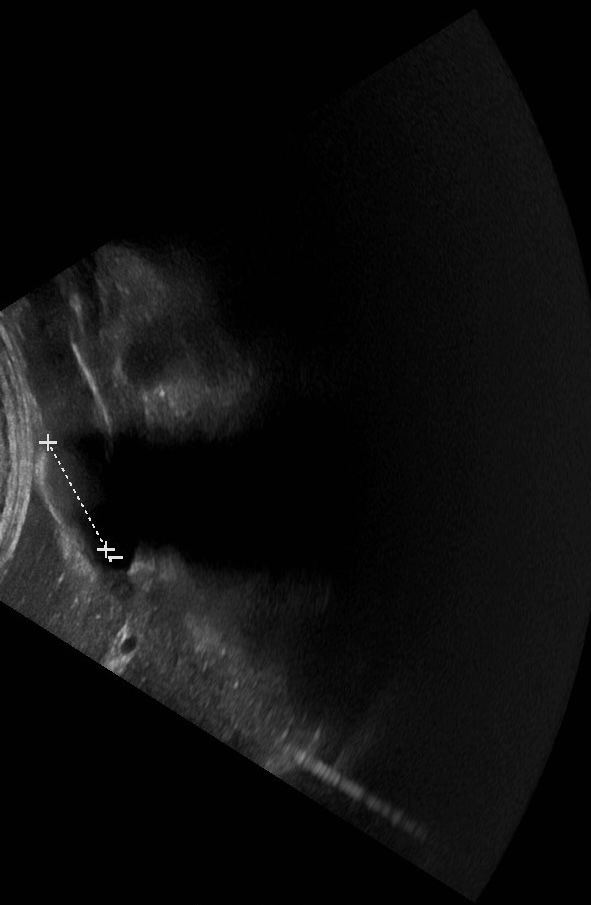

sonography image, gallstone

inside out plays with the tension between representation and physical reality. the sonography image—a blurry, clinical abstraction—contrasts with the material presence of the stone, which now exists as a tangible object outside of its original context.